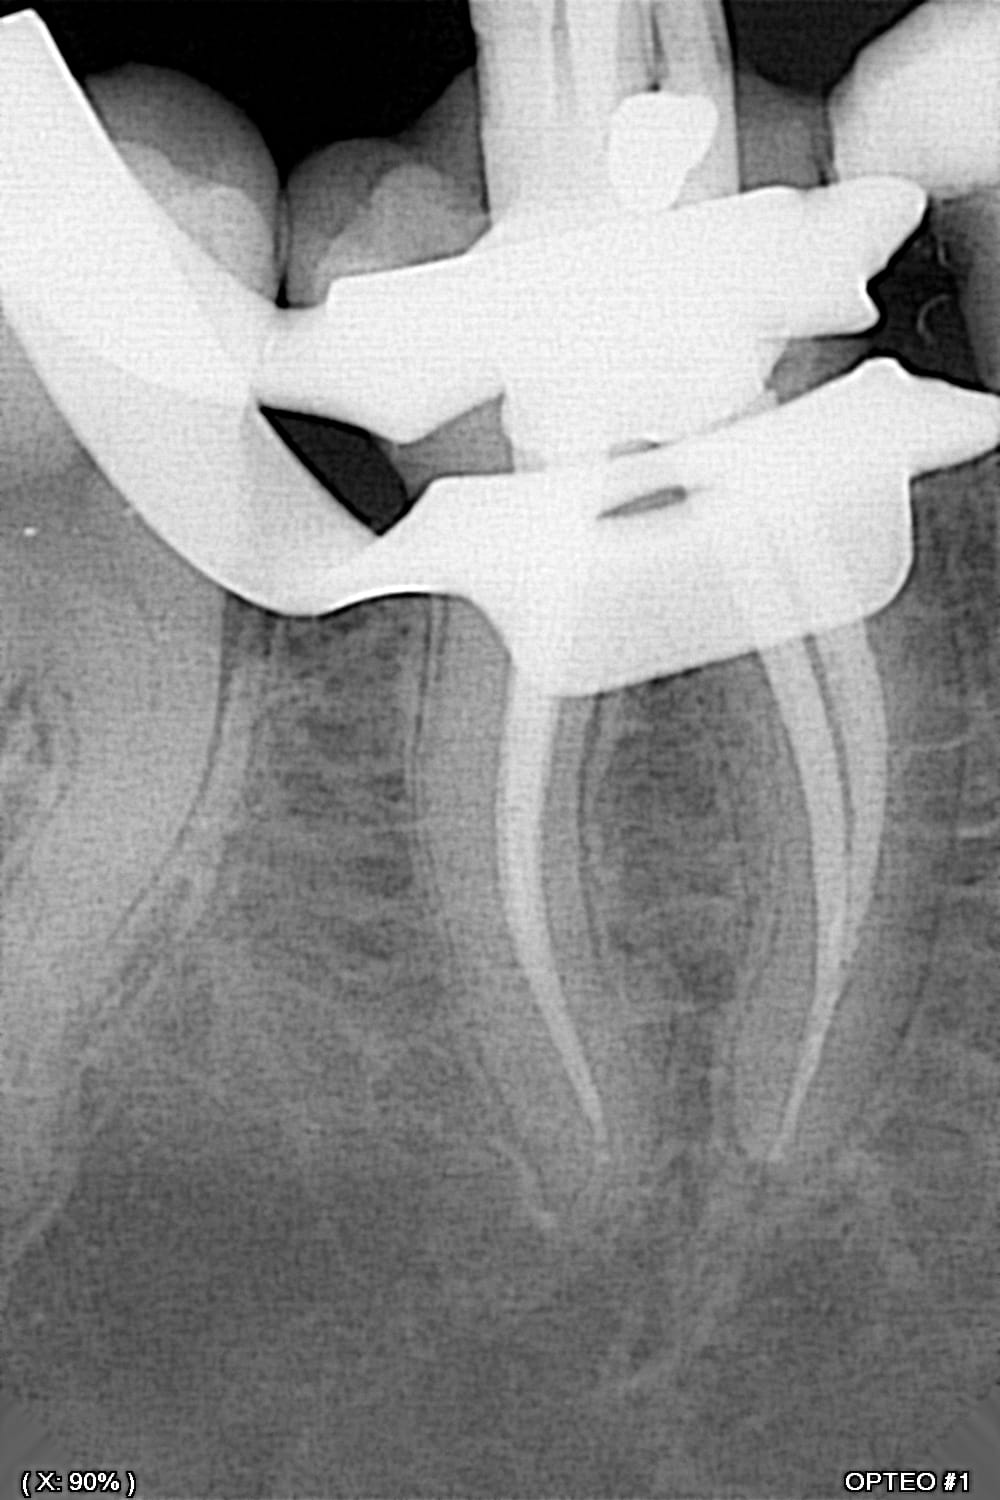

Qu'est ce que tu appelles condensation latérale seule? Tu rajoutes des cônes accessoires, hein? Pas du monocône dans une mer de ciment? J'ai un doute quand tu parles de maître cône scellé.

Donc ça c'est caca, la sécu rembourse pas?

Monocone scellé dans de la bioceram. La sécu conteste quoi ? avec ses remboursements à 2 balles ?

Effectivement, bioceram c'est pas pareil; le paradigme est différent; le monocone est légitime.

Mais il n'y a pas de condensation, c'est pour ça que je ne comprends pas ce dont parle rapelapente, un monocone sans condensation, ou une condensation latérale avec ajout de cônes accessoires.

La secu conteste le monocone sans condensation.

Si c'est bioceram, pas de soucis. Si c'est ciment classique, l'épaisseur de ciment non maîtrisée selon l'anatomie canalaire n'est à ma connaissance pas idéale. Faut que je retrouve les recos.